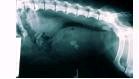

Bladder

stones are diagnosed with ultrasound or x-rays. Struvite and oxalate stones

bigger than 3mm are visible on x-rays as shown below.